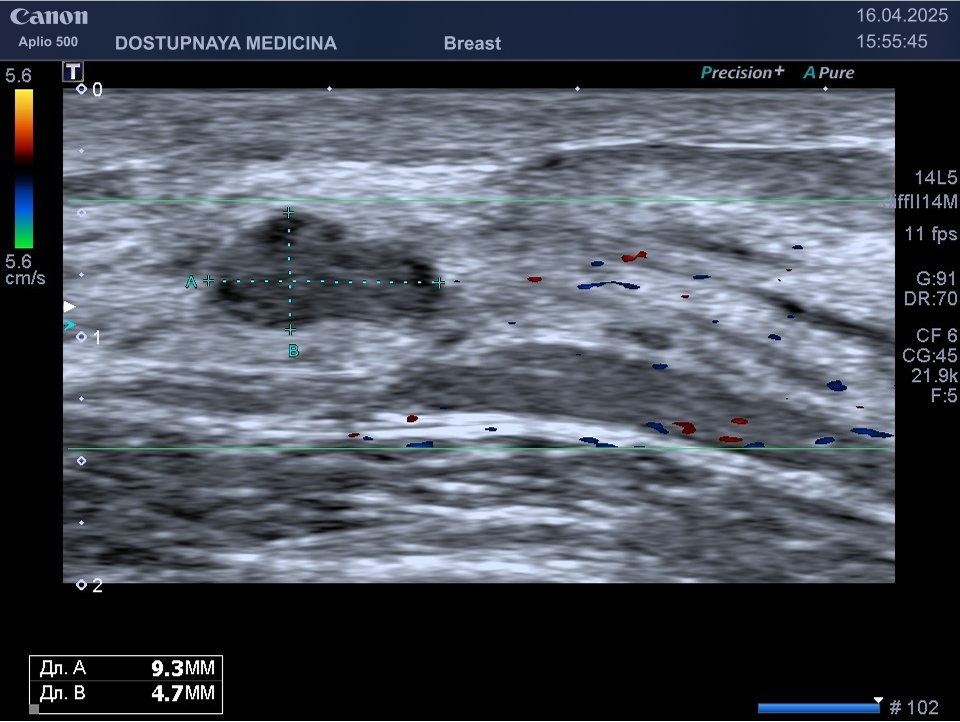

Следует проводить дифференциальную диагностику фиброаденомы с раком молочной железы, с кистой и с цистаденопапилломой. Поэтому важно повторить ультразвуковое исследование через 3 месяца, а затем при отсутствии тенденции к росту опухоли необходим УЗИ контроль через 6 месяцев.

Кисты могут воспаляться, тогда при ультразвуковом исследовании в режиме ЦДК вокруг кисты отмечается усиление кровотока, пациентка при этом жалуется обычно на уплотнение и боль в области кисты молочной железы. Воспаление кисты может привести к её абсцедированию.

При ультразвуковом исследовании в кисте может быть визуализирован папиллярный компонент с кровотоком в режиме ЦДК. Так могут выглядеть цистаденопапилломы, которые считаются аблигатным предраком.